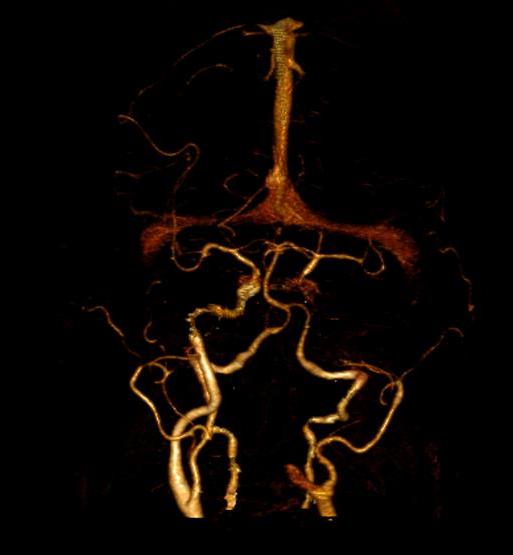

A new case of a 50-year-old female who presented with left otorrhagia caused by an internal carotid aneurysm is reported. No medical history of tinnitus, vertigo, otalgia or otorrhea. Middle ear surgery was effective in resolving bleeding and did not cause any permanent neurological deficit. High resolution computed tomography angiography is the technique of choice and, in some cases, can be complemented with a magnetic resonance angiography. Misdiagnosis of the internal carotid artery aneurysm may lead to serious morbidity because of bleeding or vascular occlusion.